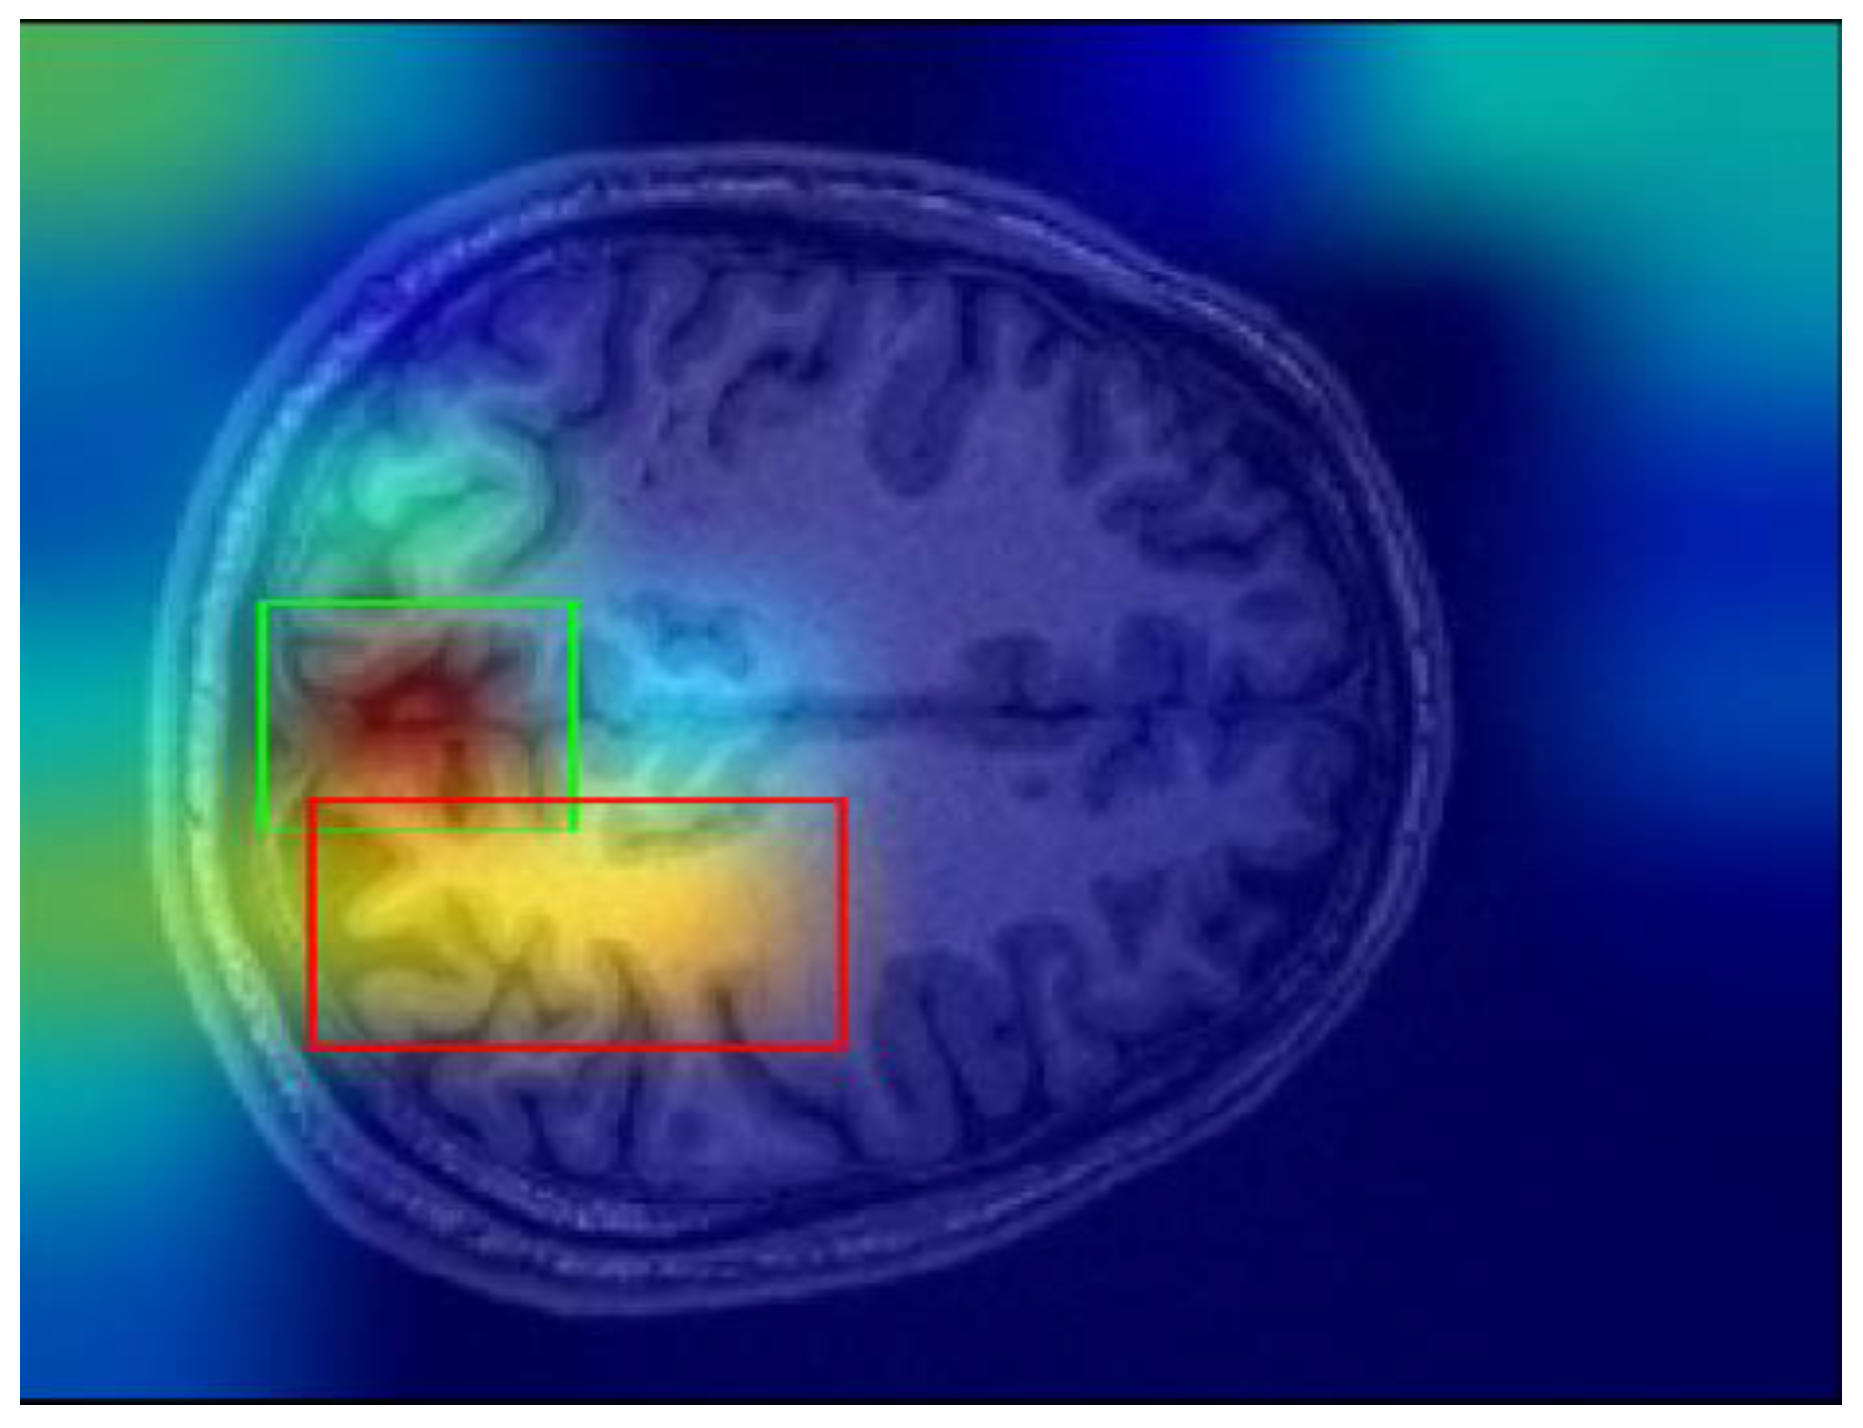

In this study, Grad-CAM was employed to identify the important regions in MR images that contributed most significantly to the classification of bipolar disorder and schizophrenia. Figure 3a,b illustrates sample images from individuals diagnosed with SCH, bipolar disorder, and their corresponding Grad-CAM heatmap results. As shown in Figure 4, the Grad-CAM heatmaps highlight the areas within each image that the model focused on during classification. After the heatmap is created, in order to identify the regions of interest highlighted by Grad-CAM, we apply a threshold value to the generated heatmap. If both red and green channel intensities exceed a value of 125, these areas are selected as important regions. This threshold value was determined through trial and error. In cases where two independent regions are identified, the region with the higher average intensity within its bounding box is prioritized as the primary area of interest. After that, we extract region-based features from the important areas determined by Grad-CAM. These features are area, centroid, eccentricity, orientation, extent, perimeter, solidity, major axis length, minor axis length, convex area, Euler number, and equivalent diameter. In addition to region-based features, statistical features such as minimum, maximum, variance, and entropy are also extracted from the important regions.

Finally, one of the most important challenges encountered in this study involves the Grad-CAM explanations. Grad-CAM visualizations sometimes yield misleading results, particularly when determining the most meaningful bounding boxes. Bounding boxes are selected based on a threshold applied to the Grad-CAM scores, and regions above the threshold values are considered significant regions. However, this threshold was determined through trial and error, and this can cause ambiguity in some cases. For instance, as shown in Figure 11, there may be multiple bounding boxes with comparable importance. While the red box surpasses the threshold and is selected, the green box, which may also be significant, is excluded. Determining which region would enhance model performance remains a challenging problem.

Figure 11. Sample Grad-CAM result.

Applsci 15 01717 g011